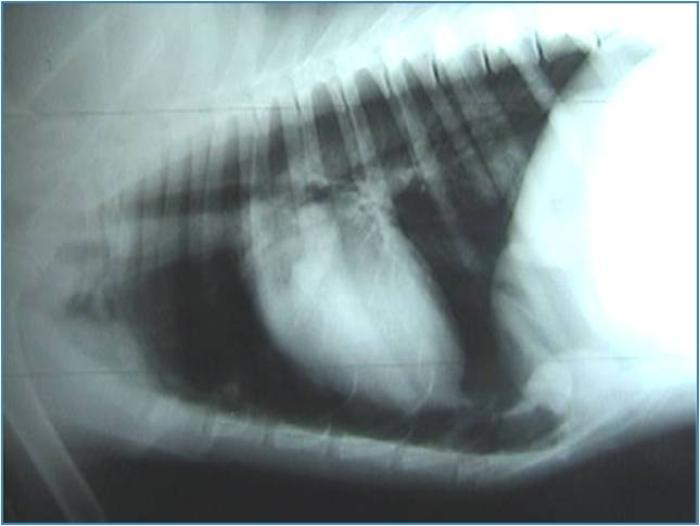

Debe llevarse a cabo con un animal estabilizado y con respiración normal (es decir, jamás con un paciente disneico o cuya oximetría de valores por debajo de lo normal). Es el método más práctico para evaluar tanto continente como contenido de la cavidad torácica, siendo conveniente solicitar al menos dos incidencias (por lo general se realiza laterolateral izquierdo o derecho y dorsoventral o ventrodorsal según el paciente lo permita). Así, se evalúa no solo si existe alguna alteración puntual de la cavidad sino también qué hemitórax se encuentra más afectado, si lo hubiera. Este método permite observar, aparte de la existencia de colectas, fracturas de costilla, rupturas diafragmáticas, presencia de masas, desviaciones viscerales, cuerpos extraños, agrandamiento de la silueta cardíaca o alteración de los patrones vasculares. Los signos radiológicos de colecta de aire son los siguientes: retracción de uno o ambos pulmones con respecto de la pared torácica, mayor densidad del pulmón debido a su colapso, desplazamiento dorsal de la silueta cardíaca.

En el caso de colectas líquidas se hallan: fisuras interlobares ensanchadas, con aumento de densidad de tejidos blandos, retracción del pulmón, quedando un espacio entre este y la pared con radiodensidad similar a los tejidos blandos, redondeamiento de la fisura costofrénica, disminución de visibilidad de la silueta cardíaca y contorno diafragmático poco definido (Figura 3A-B).